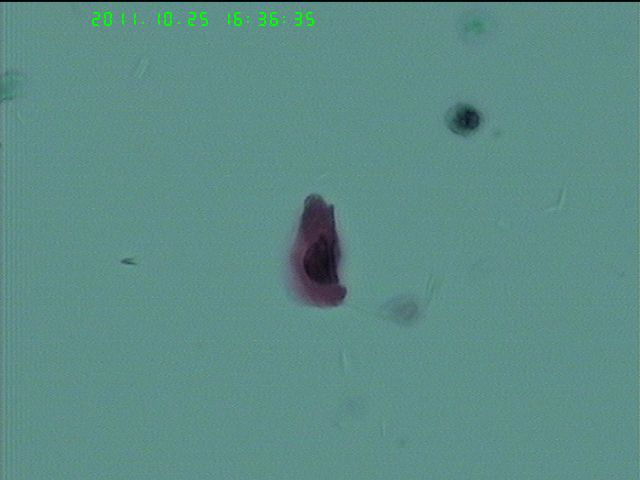

62岁女性  停经  有问题吗?细胞量稀少

老年性病人,萎缩性背景的病例,出现LSIL的病例是不多见的。

萎缩的时候,细胞很难成长到表层或者浅表层阶段,感染的HPV病毒颗粒也就没有办法完成整个生活史,因此一般不见典型的挖空细胞 萎缩性背景下,需要鉴别的为高核浆比的副基底层和HSIL,凋亡细胞与小的角化性鳞癌细胞。

此例有不少高核浆比,核异型,胞浆明显角化的细胞,报告时需谨慎,如果没有把握,ASC-H是不错的选择。

可见高核浆比细胞,核深染,核膜不规则,考虑到是老年人 报ASC-H比较恰当,达到活检目的即可。

组织学是CA